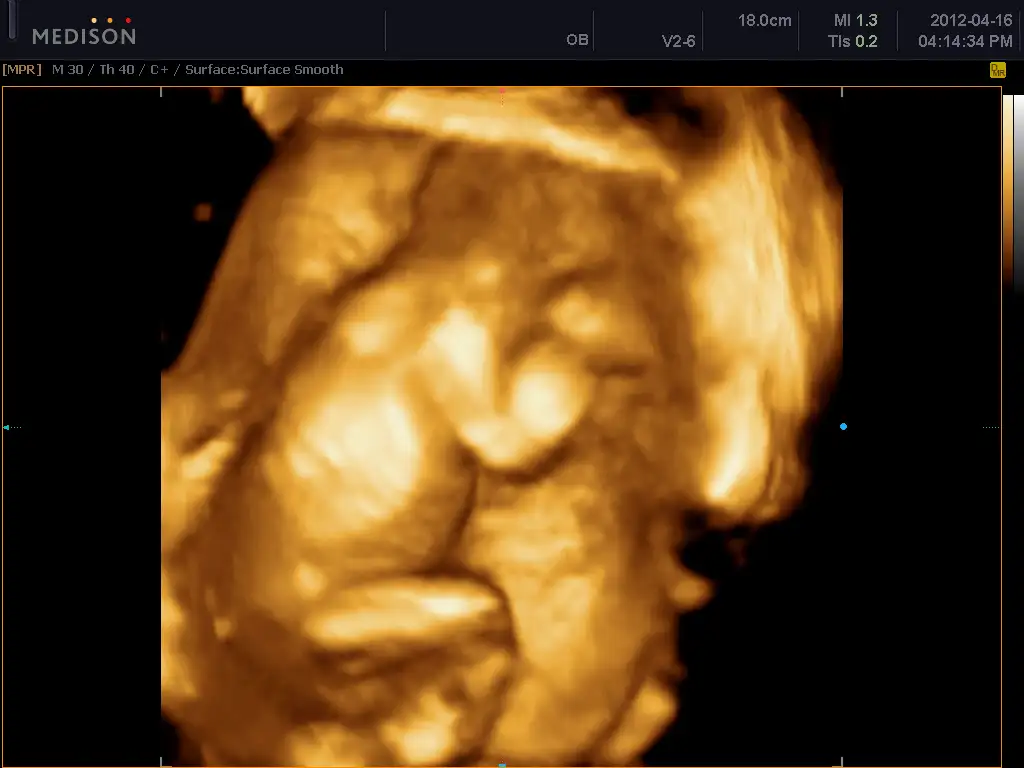

bende bugün bebeğimi ayrıntılı ultrason için 4 boyutluda görmey gititim çok belli yüzü

boydan veremem artık 5 ay bitti boy alınmıyor dedi

seninde son boydan dotoların :) bundan sonra profilden yüzden veriyorlar

bu arada bebekelr lastik gibiymiş doktor bebğimin ayağının alnında olduğunu söyledi :53:

ama ssaolsun bak bura ayak demedi sadece söyled, ben ekrandan baktım ama anlamadım

buda benim kzıım

Birsey ormak istiyorum, benim gibi bebeginin 3 boyutlu fotografını görüpte korkan var mı aranız da? Kendimi cok kötü hissediyorum cok da kafama takılıyor niye boyle hissediyorum diye ama gercekten cok ürkütücü geldi, sonra da vicdan azabı cekiyorum boyle hissettigim icin :(

macpro 3 boyutlu değil ama 4 boyutlu ultrasona sokuyor dr beni ve çooook çirkin bir bebek görüyorum. tam uzaylı. hatta en son girişimde siyah beyaz ultrason çıktılarını aldım ama 4 boyutluya gerek yok hiç vermeyin dedim Dr. a güldü. Üzülme normald eböyle değil daha derisi kalınlaşacak etlenecek dedi..:1: